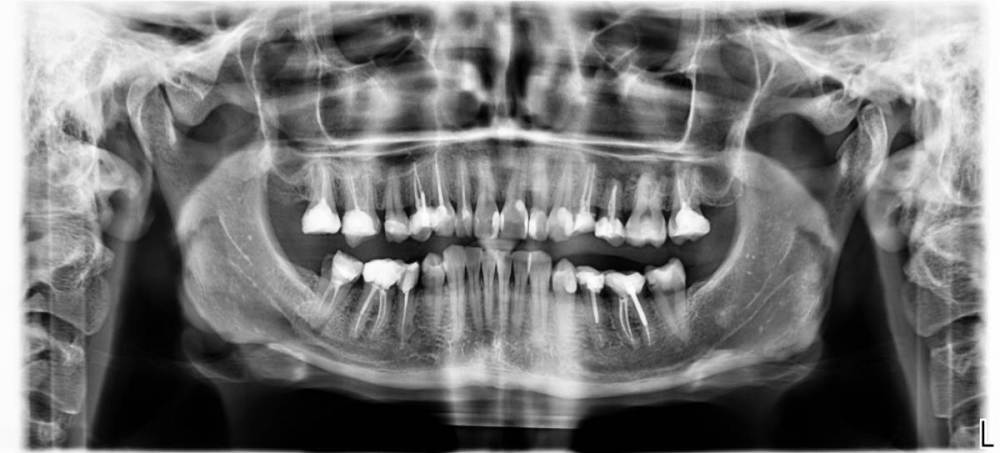

safroxa Опубликовано 10 февраля, 2023 Поделиться Опубликовано 10 февраля, 2023 Здравствуйте. Столкнулась с проблемой - откололось ползуба №24 от десны (если я правильно понимаю, верхняя челюсть, четвертый слева). На осмотре врач была удивлена, что я не протезируюсь в общем и целом (хотя до этого посещения, никто из врачей не советовал мне ставить коронки). В ходе осмотра и прицельного снимка, мне было сказано, что нужны коронки и не на один зуб. Т.е я пришла с одной проблемой, а ушла с горой проблем. Сделала панорамный снимок по рекомендации врача. Обратилась к другому врачу, который предложил поставить штифт на проблемный зуб №24 и отреставрировать его, возможно в дальнейшем поставить коронку. Снимок показала, остальные зубы у него вопросов по установке коронок не вызвали. Я в замешательстве и не знаю, что мне делать. Посоветуйте пожалуйста... Ссылка на комментарий

red_butler Опубликовано 10 февраля, 2023 Поделиться Опубликовано 10 февраля, 2023 Здравствуйте, все "мертвые" зубы нужно протезировать. А именно 1.2 13 1.4 1.6 1.7 2.4 2.5 2.7 3.5 3.6 4.5 4.6 4.7. Кроме этого требуется повторное лечение корневых каналов зубов 1.7 1.6 1.2 3.5 4.7. Лечение кариеса 3.7 По хорошему нужно сделать Кт. Вам нужен хороший ортопед. 1 1 Ссылка на комментарий

DoctorT Опубликовано 11 февраля, 2023 Поделиться Опубликовано 11 февраля, 2023 Нужно обратить внимание на состояние суставов (ВНЧС), что то мне подсказывает, что есть патологическая стираемость. Мое мнение: 1. КТ ВНЧС, в идеале МРТ ВНЧС. Для диагностики состояния суставов. 2. Санация полости рта. 3. Сплинт терапия (каппы) 4. Скорее всего, тотальное протезирование. 1 Ссылка на комментарий